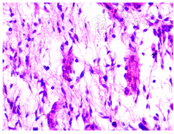

患者男,62岁,头晕、头痛、颈部不适1个月于2017年6月27日来我院就诊。既往无慢性病史。约5年前,患者行左股肿物(约6 cm × 3 cm)切除术。术后病理:软组织肉瘤,黏液型纤维肉瘤(G2),分期:T2bN0M0,ⅡB期(图1)。免疫组化:actin(-),desmin(-),S-100(+/?),Ki-67(+),CD34(+),bcl-2(+),细胞角蛋白(-),Vim(+),神经元特异性烯醇化酶(+)。术后1年余肿瘤复发,行局部肿瘤根治性扩大切除术。术后患者行局部放射治疗(60 Gy/30次),同步阿霉素+异环磷酰胺联合化疗。入院查体:锥体束征(-),颅神经(-),项强征(+)。左股近端内侧见长约20 cm手术疤痕,局部未触及肿物。卡氏评分80分,格拉斯哥评分14分。肝肾功能、血常规和凝血检查正常,乙型和丙型肝炎病毒、梅毒、艾滋病检测阴性。头部磁共振检查示,左侧侧脑室内及左侧放射冠多发类圆形占位病变,病灶明显强化,符合脑转移瘤特点;脑沟回内弥漫线样强化,以小脑沟回内为著(图2)。颈、胸和腹部CT未见占位病变。腰穿:颅压220 mmH2O,蛋白0.32 g/L,糖3.10 mmol/L,氯126.4 mmol/L,潘式反应(-),白细胞10×106/L,无红细胞。脑脊液病毒、细菌和结核菌检查均为阴性。脑脊液细胞学检查(液基细胞制片联合巴氏染色)找到肿瘤细胞(图3)。诊断为脑膜转移。行鞘内化疗及全脑放疗的综合治疗。鞘内化疗阿糖胞苷50 mg+地塞米松5 mg,每周1次。同步给予全脑放疗,采用RapidArc容积调强放疗技术,6 MV X射线,40 Gy/20次,4周完成。治疗2周后,头晕、后颈部疼痛症状明显缓解。治疗过程中,患者出现双下肢一过性麻木等腰骶部脊神经神经根刺激症状,给予对症治疗后缓解。20次全脑放疗并5次鞘内化疗后,头晕、头疼和后颈部疼痛症状基本消失,KPS评分100分。脑脊液脱落细胞学检查:找到少量肿瘤细胞。复查头部MRI较前无明显变化,颈、胸和腹部CT未见肿瘤病灶。自脑膜转移诊断至今4月余,患者无症状生存。

黏液型纤维肉瘤是一种好发于老年人肢体的常见肉瘤,易发生于皮下。组织学分级G1表现为局部侵犯,G2和G3具有潜在远处转移能力,常见转移部位为肺、骨和淋巴结[1]。本例患者为黏液型纤维肉瘤ⅡB期,组织学病理分级为G2,具有局部复发及转移倾向。

黏液型纤维肉瘤脑转移非常罕见,既往仅有少量报道[2,3,4]。脑脊液细胞学检查是明确脑膜转移诊断的金标准。本例患者脑脊液中找到的肿瘤细胞具有典型恶性特征,细胞体积大,核质明显增大,似裸核,染色质粗颗粒样,可见多核。影像学检查显示多发柔脑膜强化,为本病特征性影像学表现。另外,可见转移病灶位于脑室内,为脑膜转移提示性影像学表现。本例患者脑膜转移发生的原因,可能为肿瘤细胞血行转移所致,也可能为脑室内转移病灶肿瘤细胞脱落进入脑脊液中增殖所致[5]。本例患者既往存在纤维肉瘤病史,脑膜转移治疗前及治疗后全身检查均未见其他新发肿瘤病灶。